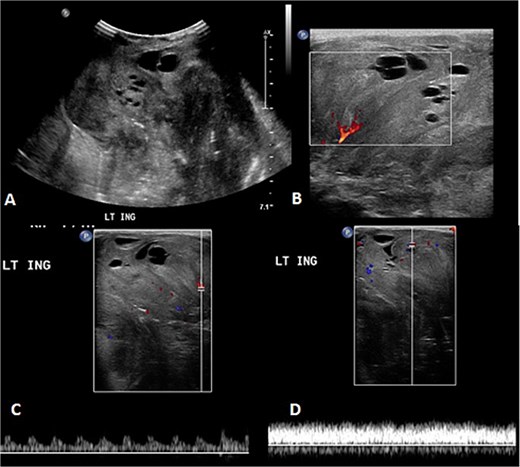

Before the presentation, the patient had an MRI done 3 weeks prior which showed a left thigh quadriceps muscle region mass measuring 3.9 × 4 × 4.7 cm. The mass showed peripheral discontinuous nodular enhancement in the early phase with centripetal enhancement in the delayed phase on postcontrast images, matching the description of a hemangioma (Fig. 2). Upon presentation, a left inguinal US was done, which showed a mass measuring 9.1 × 8.3 × 8.7 cm. The mass appeared heterogeneously isoechoic with areas of cystic changes and showed atypical manifestation on color Doppler. The US was done 3 weeks after the MRI (Fig. 3).

The follow-up ultrasound 3 weeks after MRI. (A) The gray scale image demonstrates a large heterogeneous predominantly isoechoic mass seen at the left inguinal region with multiple scattered areas of cystic changes and difficult-to-assess extent due to its size. (B–D) Color Doppler and spectral wave images show vascularity within the mass with detectable arterial and venous waveform.